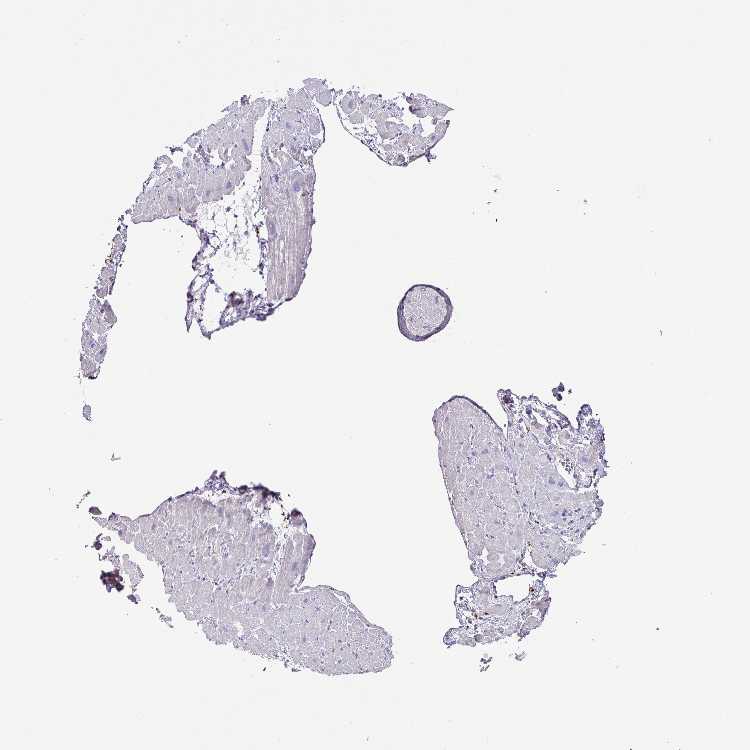

HEART MUSCLE - Antibody stainingi

Antibody staining in the annotated cell types in the current human tissue is reported as not detected, low, medium, or high, based on conventional immunohistochemistry profiling in selected tissues. This score is based on the combination of the staining intensity and fraction of stained cells.

Each image is clickable and will lead to virtual microscopy that enables deeper exploration of all samples and also displays staining intensity scores, fraction scores and subcellular localization as well as patient and tissue information for each sample.

Antibody HPA045715Antibody HPA056466Antibody CAB003697

Cardiomyocytes MediumMediumHigh